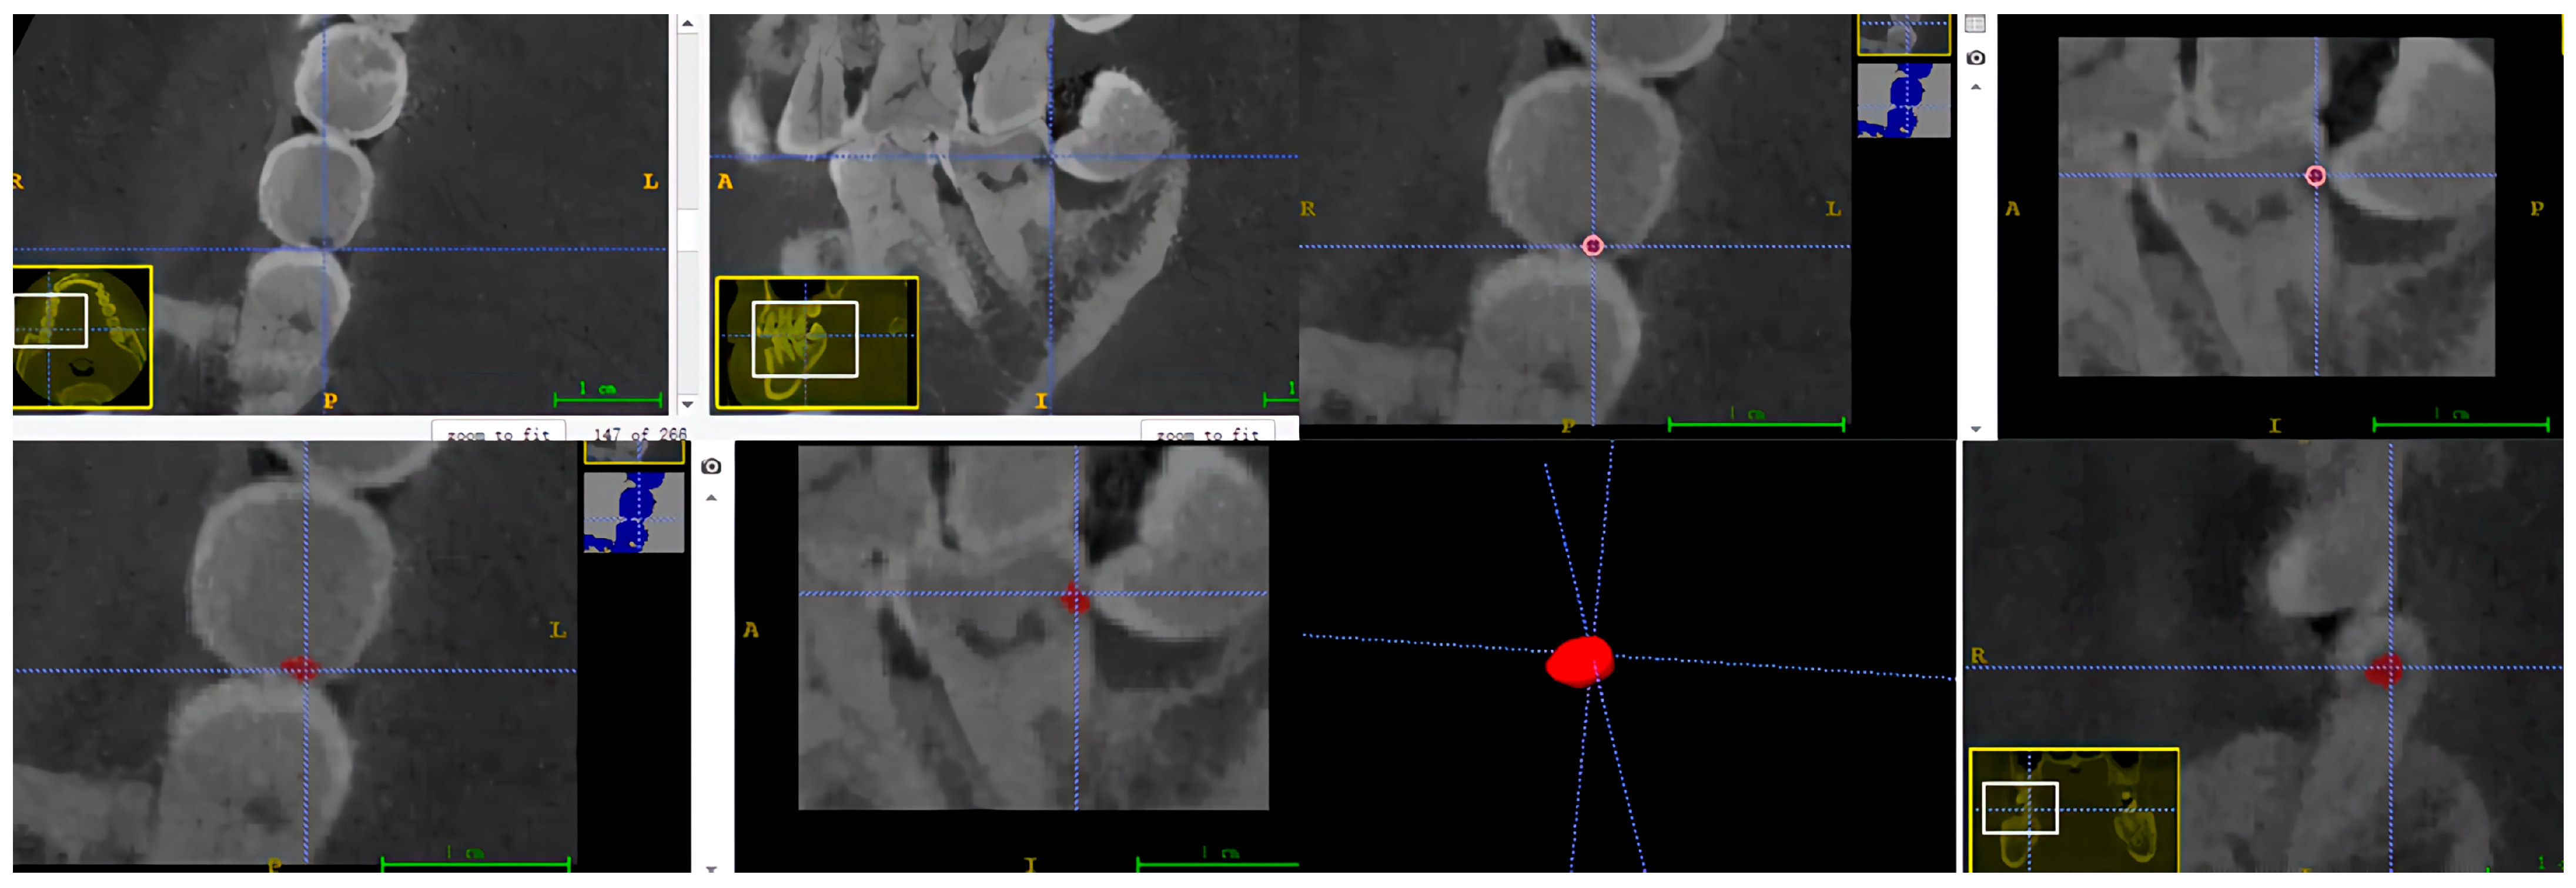

A dental radiologist with more than three years of clinical experience conducted semi-automatic labelling of carious teeth in Dataset 1 and FTG, utilizing ITK-SNAP software (V. 3.8, Cognitica, Philadelphia, PA, USA) for slice-by-slice fine adjustments (refer to Figure 1 and Figure 2). All CBCT images and their corresponding labelled data were initially stored in NIFIT format and converted into PNG files, each with a 512 × 512 pixels resolution and an 8-bit depth. Subsequently, all slices featuring carious lesions were extracted from the CBCT images and their corresponding labelled data. Each CBCT image and corresponding labelled data were assigned independently to the same identifier. Finally, slices from each patient underwent random augmentation, employing two of three techniques: affine transform stretching, random rotation, and mirroring.

Figure 1. Semi-automated annotation process using ITK-SNAP software V. 3.8. The red indicates carious lesion.

Figure 2. The manual annotation results. The red indicates carious lesions and the blue indicates the carious teeth. (a) The annotation result of a single tooth; (b) the annotation result of multiple teeth.